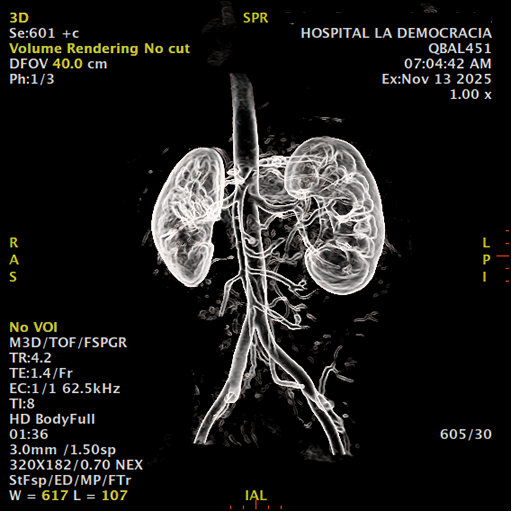

Los sistemas colectores del riñón derecho y del riñón izquierdo, muestran alteración de sus calices primarios y secundarios, mostrando dilatación, la pelvis renal y el uréter se observan de características normales lo que indica que no hay proceso obstructivo.

Se observa dilatación del sistema calicial sin proceso obstructivo compatible con una anormalidad del desarrollo de los sistemas colectores de ambos riñones, definiéndose como una “megacaliosis”

La megacaliosis congénita es una anomalía del desarrollo del sistema colector renal caracterizada por una dilatación homogénea de los cálices renales, sin dilatación de la pelvis ni del uréter y sin obstrucción demostrable. Se considera una malformación del sistema colector más que una uropatía obstructiva en sentido estricto.

Desde el punto de vista anatómico e histopatológico, la mayoría de los autores coinciden en que la base de esta anomalía es un desarrollo anómalo de la médula renal: hay hipoplasia de las pirámides medulares, papilas renales malformadas o aplanadas, y acortamiento de los túbulos colectores, lo que se traduce en cálices más numerosos, ensanchados y de contornos facetados o “en trébol”.